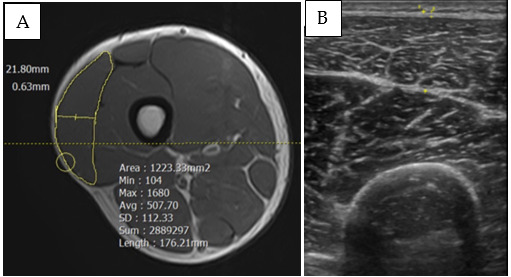

Methods: Eighteen active participants were recruited and randomly assigned to the HI (n = 10) or MIX (n = 8) groups, undergoing different 6-week resistance training programs. The training volume set was equated and progressively increased from three sets in weeks 1 and 2 to six sets, and eight sets in weeks 3-4 and 5-6, respectively. Three specific regions of vastus lateralis were assessed by magnetic resonance imaging (MRI) and ultrasound imaging (US) during pre-and post-intervention.

Results: Statistical analysis revealed statistically significant increases in muscle area at the proximal (HI: Δ12%, MIX: Δ9.2%), middle (HI: Δ8.7%, MIX: Δ9.0%), and distal (HI: Δ14%, MIX: Δ13%) regions. Additionally, both HI and MIX groups showed statistically significant increases in the sum of muscle thickness post-intervention (HI: Δ12%, MIX: Δ19%) and in the sum of fascia thickness post-intervention (HI: Δ27%, MIX: Δ54%). Despite the MIX group training with higher volume load, no statistical differences were observed between groups for any week.